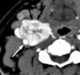

Carotid body tumor

A paraganglioma is a rare neuroendocrine neoplasm that may develop at various body sites (including the head, neck, thorax and abdomen). When the same type of tumor is found in the adrenal gland, they are referred to as a pheochromocytoma. [Source: Wikipedia ]